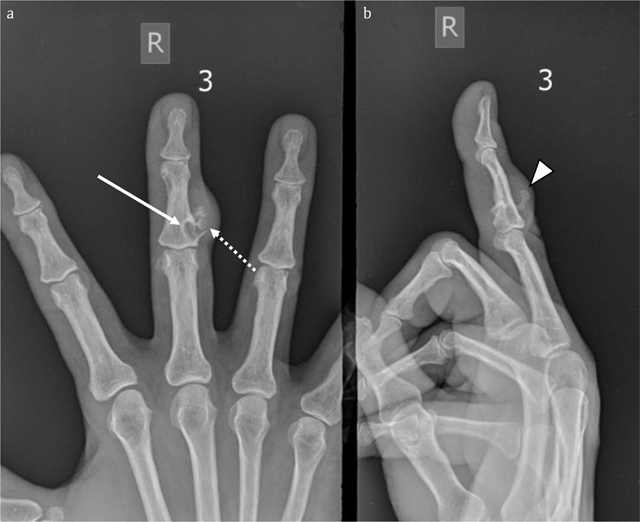

Figure 6

Case 2 – Conventional radiographs of the right third finger. AP (a) and lateral view (b). Note a juxta-cortical radiolucent lesion at the dorso-ulnar aspect of the middle phalanx. The smaller intramedullary part is well-delineated and surrounded by a rim of sclerosis (arrow in a). The larger exophytic component consists of a bony protuberance with adjacent soft tissue swelling (arrowhead in b). There is focal breakthrough of the cortex (dotted arrow in a).